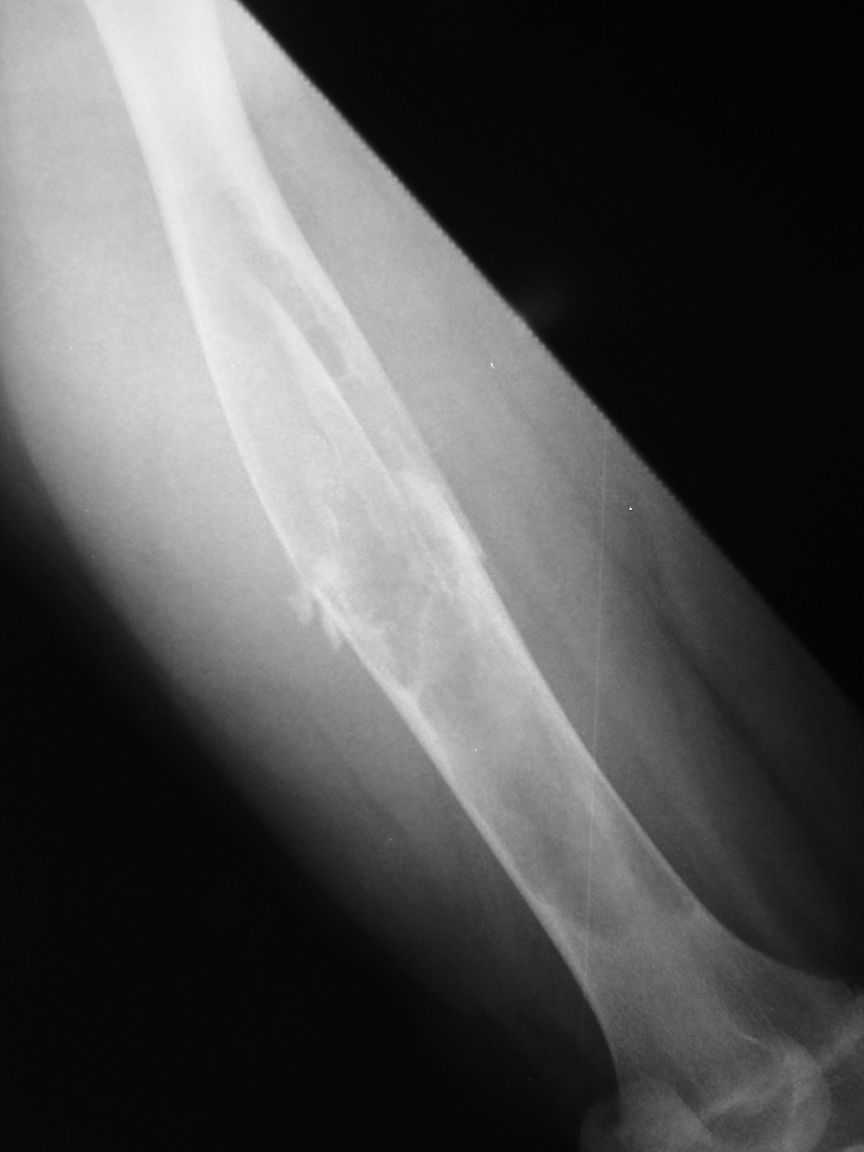

The attached xrays are of a 13 year old girl, who presented to us with a history of trivial trauma.

X-rays showed a pathological fracture right femur

through a large radioluscent expansile lesion. All

blood investigations are normal. Clinically no other positive findings. We assume this to be a case of fibrous dysplasia, and plan to do a biopsy from the site. Would like your opinion regarding any other possibility in the diagnosis and treatment options.